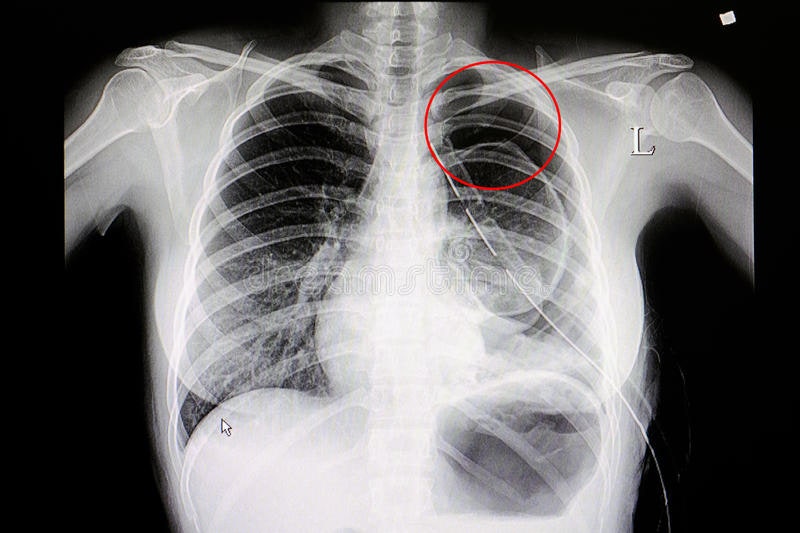

전유성 씨 사망 보도에서는 “폐기흉 증세 악화”라는 표현이 많이 등장했어요. 보통 “폐기흉”보다는 “기흉”이라는 표현이 의학적으로 더 일반적이고, 흉막강 내 공기가 유입되는 현상을 의미합니다.

✅ 기흉(폐기흉)의 정의

- 폐와 흉막 사이 공간(흉막강)에 공기가 유입되어 폐가 압박당해 팽창하지 못하는 상태

- 호흡곤란, 흉통 등을 유발할 수 있고, 심한 경우 응급 상태로 발전

- 자연발생형(자발성 기흉)과 외상성 기흉으로 나눌 수 있음